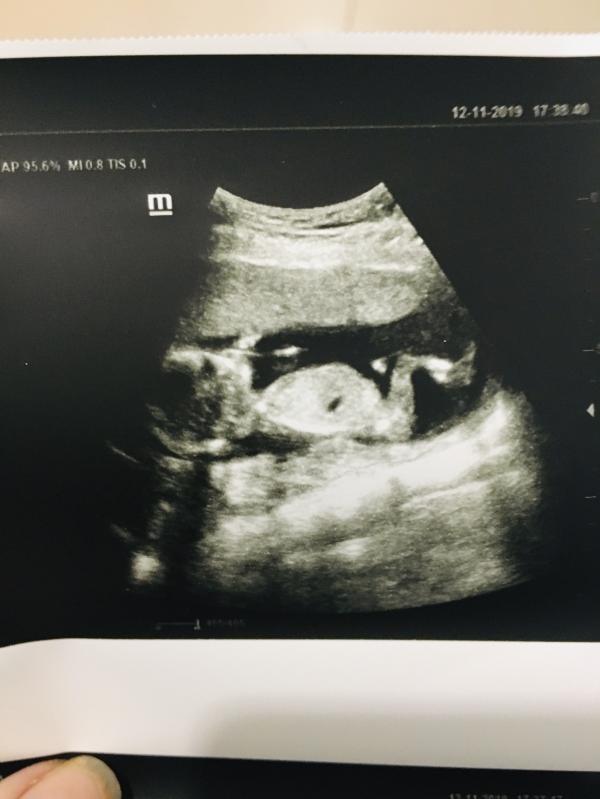

Были мы на узи)💜 муж сидел не дышал не отрывал глаза от экрана. Папе сообщили кого ждём. Так что сюрприз не получился . Зато эмоции не передать)

@tatusya2810, @mamaay, @vedana, сына ждём